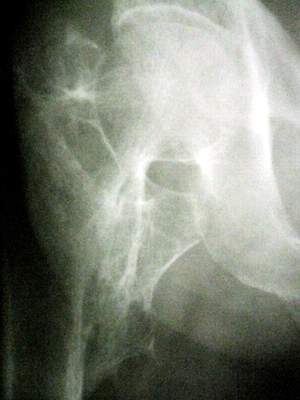

以下是引用lkc8963在2008-12-19 21:19:00的发言:[br]左?右?患侧大转子上移,股骨颈骨质浓杂,髋周见多发条片状骨化影,以小转子为著,多为陈旧性股骨颈骨折后改变并骨化性肌炎.请咨询既往史!